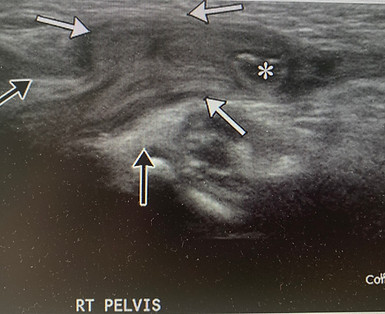

Extremity Arterial (Artery) Ultrasound

Arteries are the blood vessels that carry blood from your heart to a specific organ or body part. Extremity artery ultrasounds evaluate blood flow in the limbs (arms or legs). The goal of these ultrasounds are to determine if there is any plaque buildup or whether a blockage has occurred that would limit the flow going to a body part. The photo above is a leg arterial.